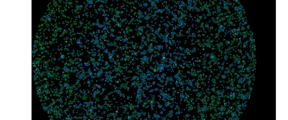

HeLa cells labeled with DAPI, Alexa 488 - Ki67, Alexa 555 - Phalloidin, Whole Cell Stain. 521nm = Red Channel, 612nm = Green Channel, 673 = Blue Channel

To demonstrate their design, the researchers applied various dyes that adhere to specific molecules within a cell sample. These dyes respond to laser light by fluorescing at specific frequencies so they can be detected and localized with high precision. Each microlens then looked at a very small part of the sample, an area about 0.6 by 0.1 millimeters in size. The raw data produced by this was a series of small images roughly 1,200 by 200 pixels wide.

These individual multicolor images were then stitched together into a large mosaic image. By simultaneously imaging 13 separate colors bands, the dataset produced was nearly 17 billion pixels in size.